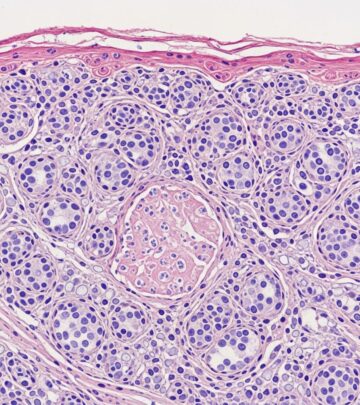

Radiographic Investigations In Melanoma: Essential Imaging Guide